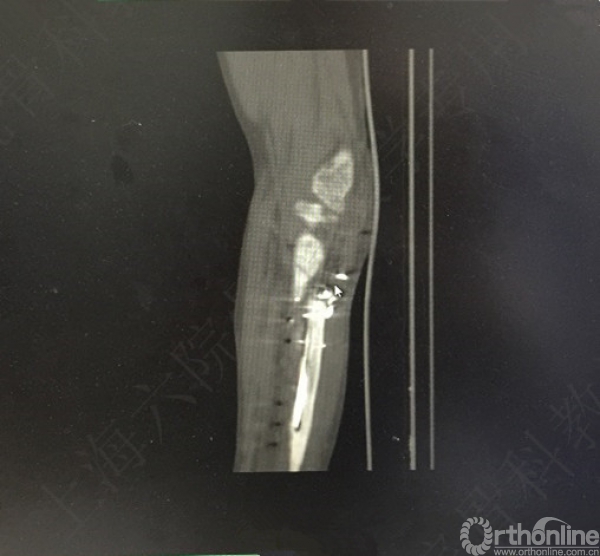

患者左尺桡骨多发骨折伴肘关节脱位,术后2年,桡神经损伤,左拇指伸受限。

X线及CT示:左尺桡骨骨不连,尺骨力线差,成角,桡骨头脱位,创伤性关节炎。

患者择期行左尺桡骨取原内固定+切开复位内固定术+髂骨异体骨植骨+桡骨头切除术。

术后X线片示:左尺桡骨骨不连术后,对位对线可,内固定牢靠,桡骨头切除,肘关节在位。

医方第一次术后,未能纠正骨折力线,未发现桡骨头脱位,手术方式和操作欠妥当。存在对疾病评估不足,漏诊,手术方式不当,手术操作不当,术后并发症观察及处理不当等过失。